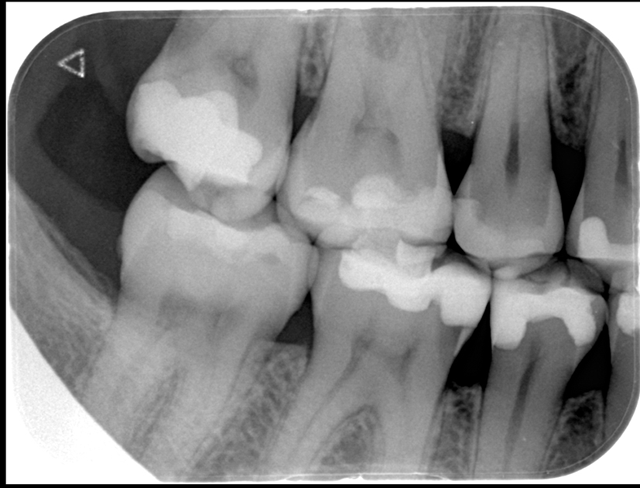

After initial X-ray (Fig. 2) and rubber dam isolation (Fig. 3), the previous restoration was carefully removed with a 1015 diamond bur (KG Sorensen) in order not to compromise the adjacent tooth. A metal matrix was used for protection. The cavity was cleaned with pumice (Fig. 4).

Fig. 3 Fig. 4